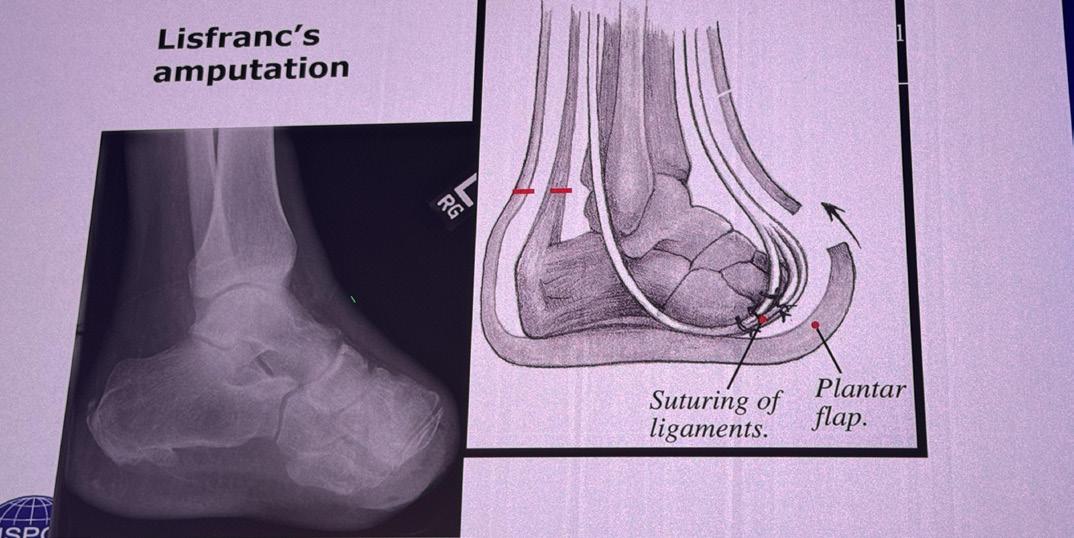

30 Epiphysen: Amputationer av nedre extremiteten

32 Epiphysen: Ortoplastik